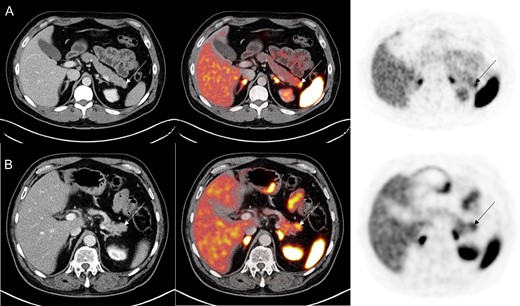

(A) 68Ga PET/CT DOTATATE demonstrating increased DOTATATE uptake (SUVmax 9.7) in the distal pancreas without underlying pancreatic mass in the first case study. (B) In the second case study, 68Ga PET/CT DOTATATE revealed increased DOTATATE uptake (SUVmax 7.6) in the pancreatic tail without any CT abnormality.

A 48-year-old Caucasian male with a medical history significant for hypertension was referred to the general surgery clinic for chronic abdominal pain for the past 6 months. The patient was suffering from nausea, postprandial facial flushing and crampy/colicky epigastric pain radiating to the RLQ. Initial laboratory work up including complete blood count, complete metabolic panel, serum CA-19-9, serum CEA, urinary 5-HIAA, serum chromogranin A and serum neuron specific enolase were all unremarkable. Additionally, right upper quadrant ultrasound and CT abdomen/pelvis were unremarkable. However, the patient symptoms persisted, and therefore a 68Ga DOTATATE PET/CT scan was ordered. Imaging revealed increased DOTATATE activity (SUV 9.7) in the distal pancreatic tail without an underling mass on CT (Fig. 1A). EUS fine needle aspiration was unremarkable. Additional laboratory analysis revealed elevated C-peptide (4.9 ng/ml) and proinsulin levels (76 pmol/l), concerning for an insulinoma. In addition, a HIDA scan showed a gallbladder ejection fraction of 34%, consistent with chronic cholecystitis.

A 68-year-old male with a medical history for hypertension and type 2 diabetes mellitus, was referred to the general surgery clinic with three bouts of acute pancreatitis of unclear etiology from February 2017 to March 2018. He had intermittent severe postprandial epigastric pain and nausea. Patient denied other symptoms. Initial laboratory work up was unremarkable except for an elevated chromogranin A (393 ng/ml). CT abdomen and pelvis as well as magnetic resonance cholangiopancreatography were unable to identify any lesion. Therefore, the patient underwent a 68Ga DOTATATE PET/CT scan which revealed increased uptake in the distal pancreas (SUVmax 7.6) without any underling lesion (Fig. 1B). EUS fine needle aspiration showed no abnormalities. Given the multiple bouts of acute pancreatitis, he was recommended to have a laparoscopic distal pancreatectomy and splenectomy. Intraoperative ultrasound demonstrated a normal pancreas. Pathology revealed a NET (10 mm in size) and margins were negatives. Eleven benign lymph nodes were resected. His 2-week postoperative follow up in late April 2018 was unremarkable. He denied new symptoms and previous symptoms have resolved. No imaging or laboratory work up was done at this time.

Although these markers are highly sensitive and specific for NETs [9], there was no morphological evidence of any lesion. However, both did have functional evidence of NET on the distal pancreas (Fig. 1). EUS studies were unremarkable and unable to give a tissue diagnosis, which may have been secondary to the presence of pancreatitis or the location of the lesions in the distal pancreas. The patients underwent laparoscopic distal pancreatectomy and splenectomy and there was microscopic evidence for NET in the pathologic specimens.